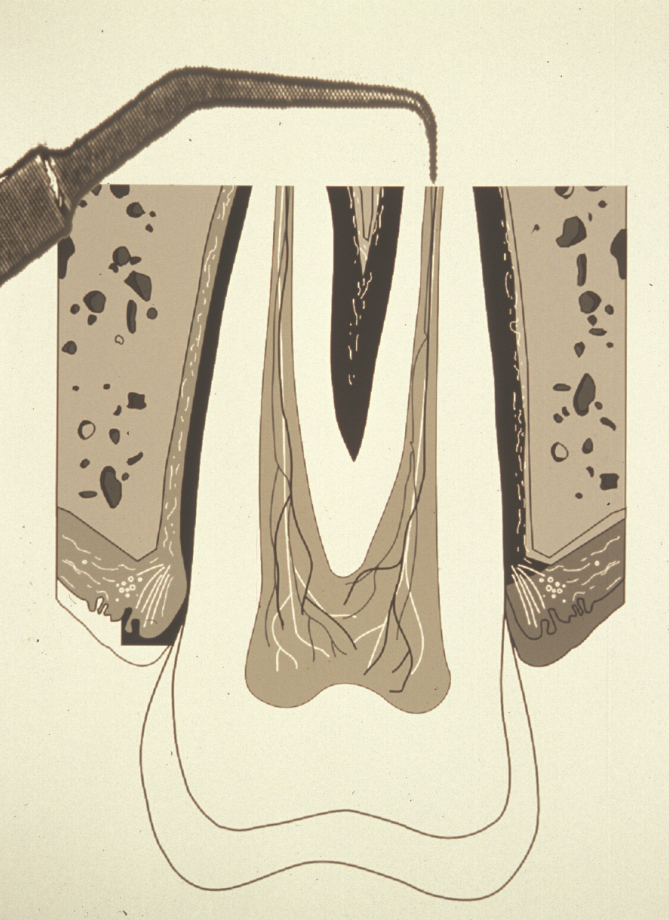

The ideal root end cavity preparation is defined as a class I preparation, at least 3 mm into root dentine with walls parallel to and coincident with the anatomic outline of the pulpal space. A contra-angled slow speed microhead handpiece with a small round burr has conventionally been used to prepare the cavity, but this does not relate to the anatomy of the pulp and often the apical dentine is weakened by unnecessary over- enlargement. There is also a considerable risk of perforating the root-end. Therefore, specifically designed ultrasonic instruments have been developed to create an accurate preparation. Their small tip size allows much greater access than even the microhead handpiece (Figure 4).

Ultrasonic instrumentation enables the isthmus (narrow connection) running between some canals to be prepared and sealed. This isthmus is often a reservoir for bacteria that have not been removed during conventional root canal therapy (Figure 5). In many developed countries the use of magnification and piezo (ultrasonic ) instruments are the accepted standard.